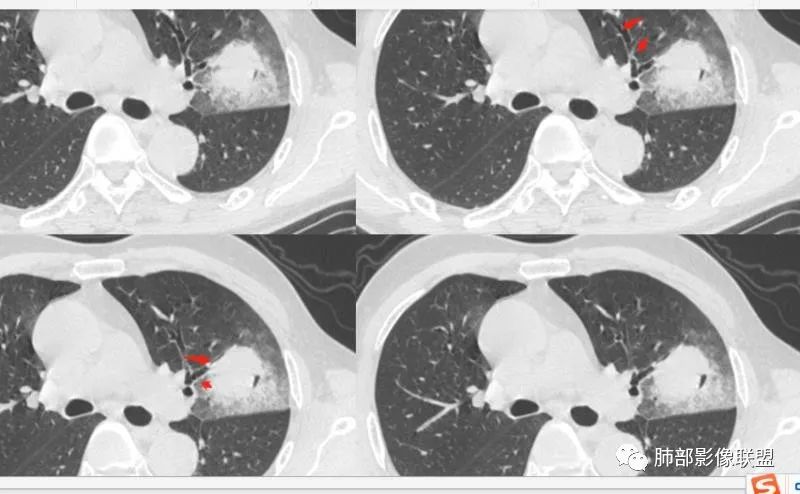

左肺上叶类圆形软组织影,边界较清楚,其内密度均匀,外侧缘可见空气新月征,并可见点状钙化,增强扫描可见均匀强化,病灶周围可见磨玻璃渗出性密度影,斜裂侧光滑平整。考虑炎性病灶,以肉芽肿性炎症为主(如真菌性肉芽肿),鉴别结核(无卫星灶,无多态性),肺癌(无毛刺,分叶等恶性征象,)细菌性炎症(密度一般不这么致密,很少钙化及空气新月征)。 医学百科网 | YxBaike.Com

老年男性,血糖升高六年,反复咳痰咳嗽3周,左肺上叶近斜裂类圆形肿块影,边缘伴磨玻璃影,边界不清。内部可见支气管走行、钙化、小空洞,叶间裂局部膨隆,增强扫描轻度强化,内部可见小的低密度区,边界尚清。考虑为炎性病变可能性大。 医学百科网 | YxBaike.Com

左肺叶裂旁实变影,宽基底与叶裂胸膜相连,边缘平直,部分略膨隆,病灶近段及上段支气管深入病灶内,部分壁略增厚,远端支气管截断,似有小空泡,壁规则,内部可见高密度钙化,周围可见模糊的GGO,血象正常,考虑结核(NTM),鉴别隐球菌,奴卡,放线菌。 医学百科网 | YxBaike.Com

老年男性,66,反复咳嗽、咳痰3月。糖尿病,血象不高。

胸部CT:左肺上叶类圆形肿块影,边界较清楚,密度较均匀,内可见小片坏死、偏心空洞、空气新月征、点状钙化,周围晕、絮状渗出、边缘模糊,支气管扩张、充气征、支气管进入病灶堵塞,叶裂牵拉明显,增强扫描中度均匀强化,纵隔可见淋巴结。考虑:炎性病灶,肉芽肿性炎症,曲霉?毛霉?鉴别:TB,淋巴瘤。

左上肺类圆形肿块影,边界较清楚,支气管通畅略扩张,周围磨玻璃影,其内密度均匀,外侧见空气新月征,且见点状钙化。叶间裂光滑稍膨隆。老年男性,糖尿病,高血压,痰培养克雷伯菌。综合考虑炎性病灶,克雷伯合并真菌感染,曲霉。结核合并真菌。鉴别肺癌合并感染。 医学百科网 | YxBaike.Com

左肺上叶类圆形软组织影,边界稍模糊,其内密度均匀,外侧缘可见空气新月征,并可见点状钙化,增强扫描渐进性强化,病灶周围可见磨玻璃影,斜裂侧光滑平整,气管未见明显闭塞,淋巴结未见肿大,糖尿病患者,首先考虑感染性变,结核并曲霉?

1、团片状,实行密度区外观整体圆顿,位于上叶尖后段与下舌段区间。局部膨隆,但未见分叶,肿瘤多见。 医学百科网 | YxBaike.Com

2、偏心空腔病灶,气腔略呈新月形,壁不规则,腔内结节相对密实,明显强化且不均,支持新生物而非曲菌球等。炎性空洞多有强化环。

3、病变强化较明显,其内隐约显示多发小斑片状无强化灶,可疑边界不清小灶坏死区。病灶内血管影浅淡、模糊不规则。

4、支气管改变:上舌段支气管远段延入部分稍示僵硬。尖后段见分支支气管阻塞,恶性多见。

5、周围磨玻璃,3个月后逐渐转为密实,应符合当初附壁生长为主,且逐渐向实体成分转换。

6、病变长轴平行且受限于胸膜,外围大内带小,符合外朝内发展病变。“腔内结节状明显强化”加之支气管改变有力支持新生物诊断。如此大范围边界不清的磨玻璃影让人浮想联翩。如此大范围病灶,肺门纵隔未见肿大淋巴结也让人意外。